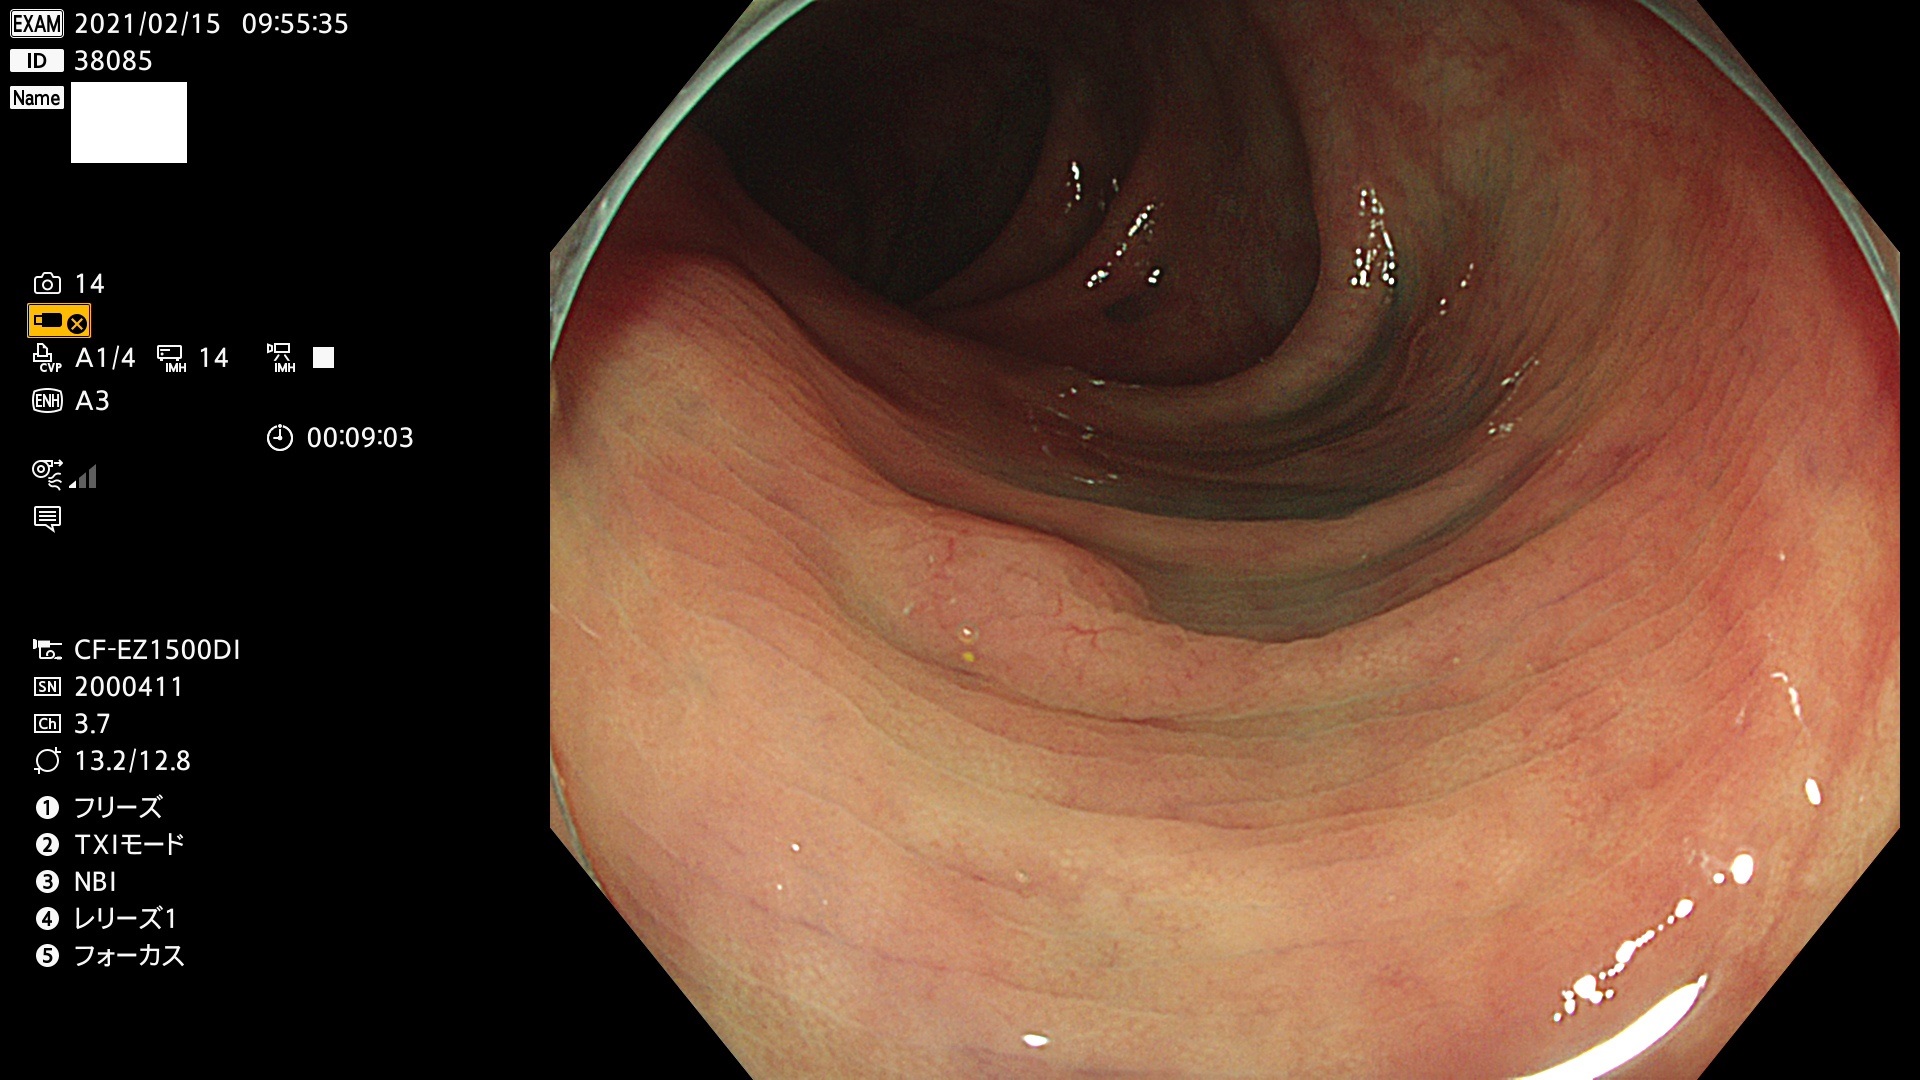

38001 38002 38003 38004 38006(SSAPのみ) 38007 38008 38009 38010 38012 38013 38014 38016 38018 38020 38021 38025 38026 38029 38032 38033 38034 38035 38036 38037(SSAPのみ) 38039 38043 38044 38048 38049 38050 38052 38055 38056 38057 38058 38059 38064(SSAPのみ) 38065 38068 38069 38070 38071 38072 38074 38075 38076 38078 38079 38080 38082 38083 38084 38085(SSAPのみ) 38086 38087 38088 38089 38090 38091 38092 38093 38094 38097 38098 38099

発見困難で危険性の高い平坦型病変(上記100名より抽出)